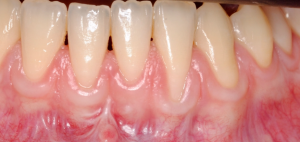

Os enseñamos este nuevo caso el Dr. Arturo Sánchez Colodro en nuestra clínica dental de Jaén, nos muestra un caso donde se puede apreciar con mucha claridad el antes y después de un caso de recesiones inferiores. Este caso ha sido tratado con la última y más avanzada tecnología en digitalización dental.

Exploración intraoral inicial:

Fotografías del proceso: